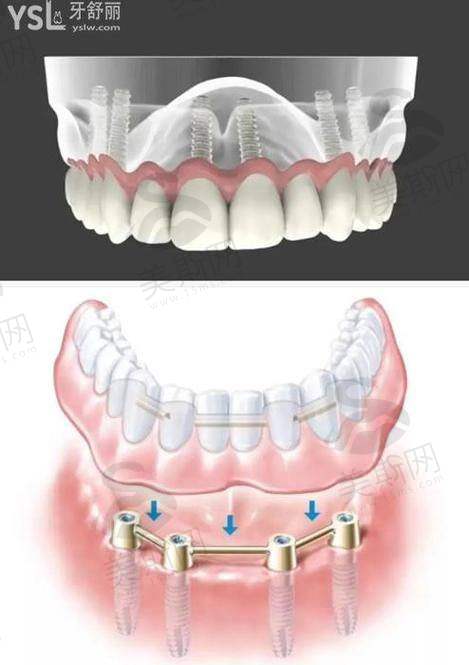

1. 数字化精细种植牙:采用德国卡瓦CBCT三维扫描定位,搭配3D导板实现误差<0.1mm精细种植,支持即刻负重(单颗/多颗缺失当天戴牙)、All-on-4半口/全口种植(24小时修复咬合)及骨量不足病例(骨增量、上颌窦提升、穿颧种植);

3. 适应症广泛:针对全口牙槽骨萎缩患者,创新应用“穿颧种植技术”,无需植骨即可实现全口修复;半口缺失患者采用All-on-4技术,仅需4颗植体即可修复12-14颗牙齿功能,费用较传统种植节省40%;

4. 长期稳定性:选用瑞典诺贝尔、瑞士ITI等骨结合率高的种植体,搭配个性化基台与全瓷冠,临床数据显示5年成功几率达98.6%,并提供10年质保+终身免费复查服务。该技术尤其适合高龄、骨条件差及对修复时间要求高的患者,目前已累计完成超2000例即刻负重病例,其中包括82岁全口缺失患者24小时修复咬合功能的成功实例。